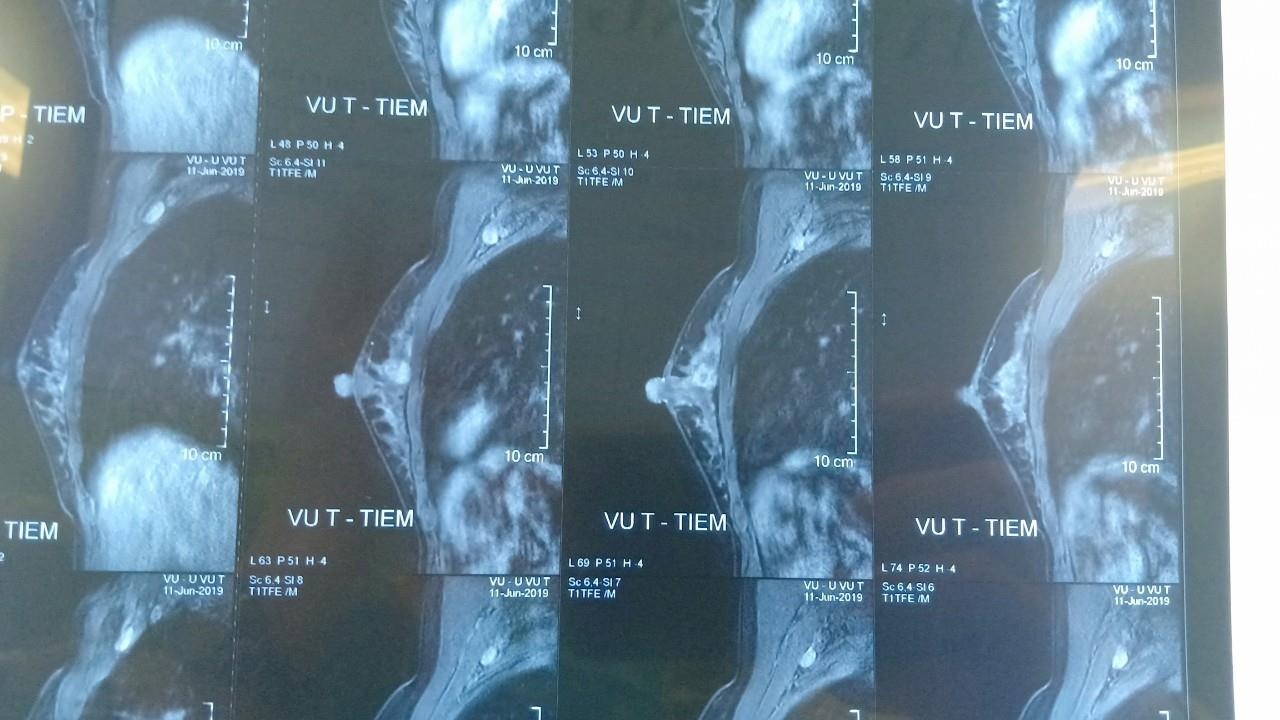

| Hình ảnh phim chụp khối u của bệnh nhân trước khi phẫu thuật. Ảnh: MT. |